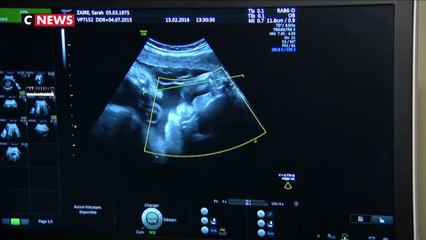

Bientôt la fin du parcours du combattant pour les couples lesbiens et les femmes célibataires qui souhaitent bénéficier de la PMA ? Pour la 3ème fois, les députés ont débattu sur la loi à l'Assemblée nationale.